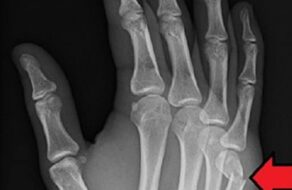

Сээрний яс гараараа цохисноос үүдэн гар, сарвуугаа гэмтээх тохиолдол гарч байна. Энэ асуудалтай холбоотойгоор мэргэжлийн эмч зөвлөмж өгснийг хүргэе. Гэмтэл, согог судлалын үндэсний төвийн Гар сарвуу нөхөн сэргээх бичил...